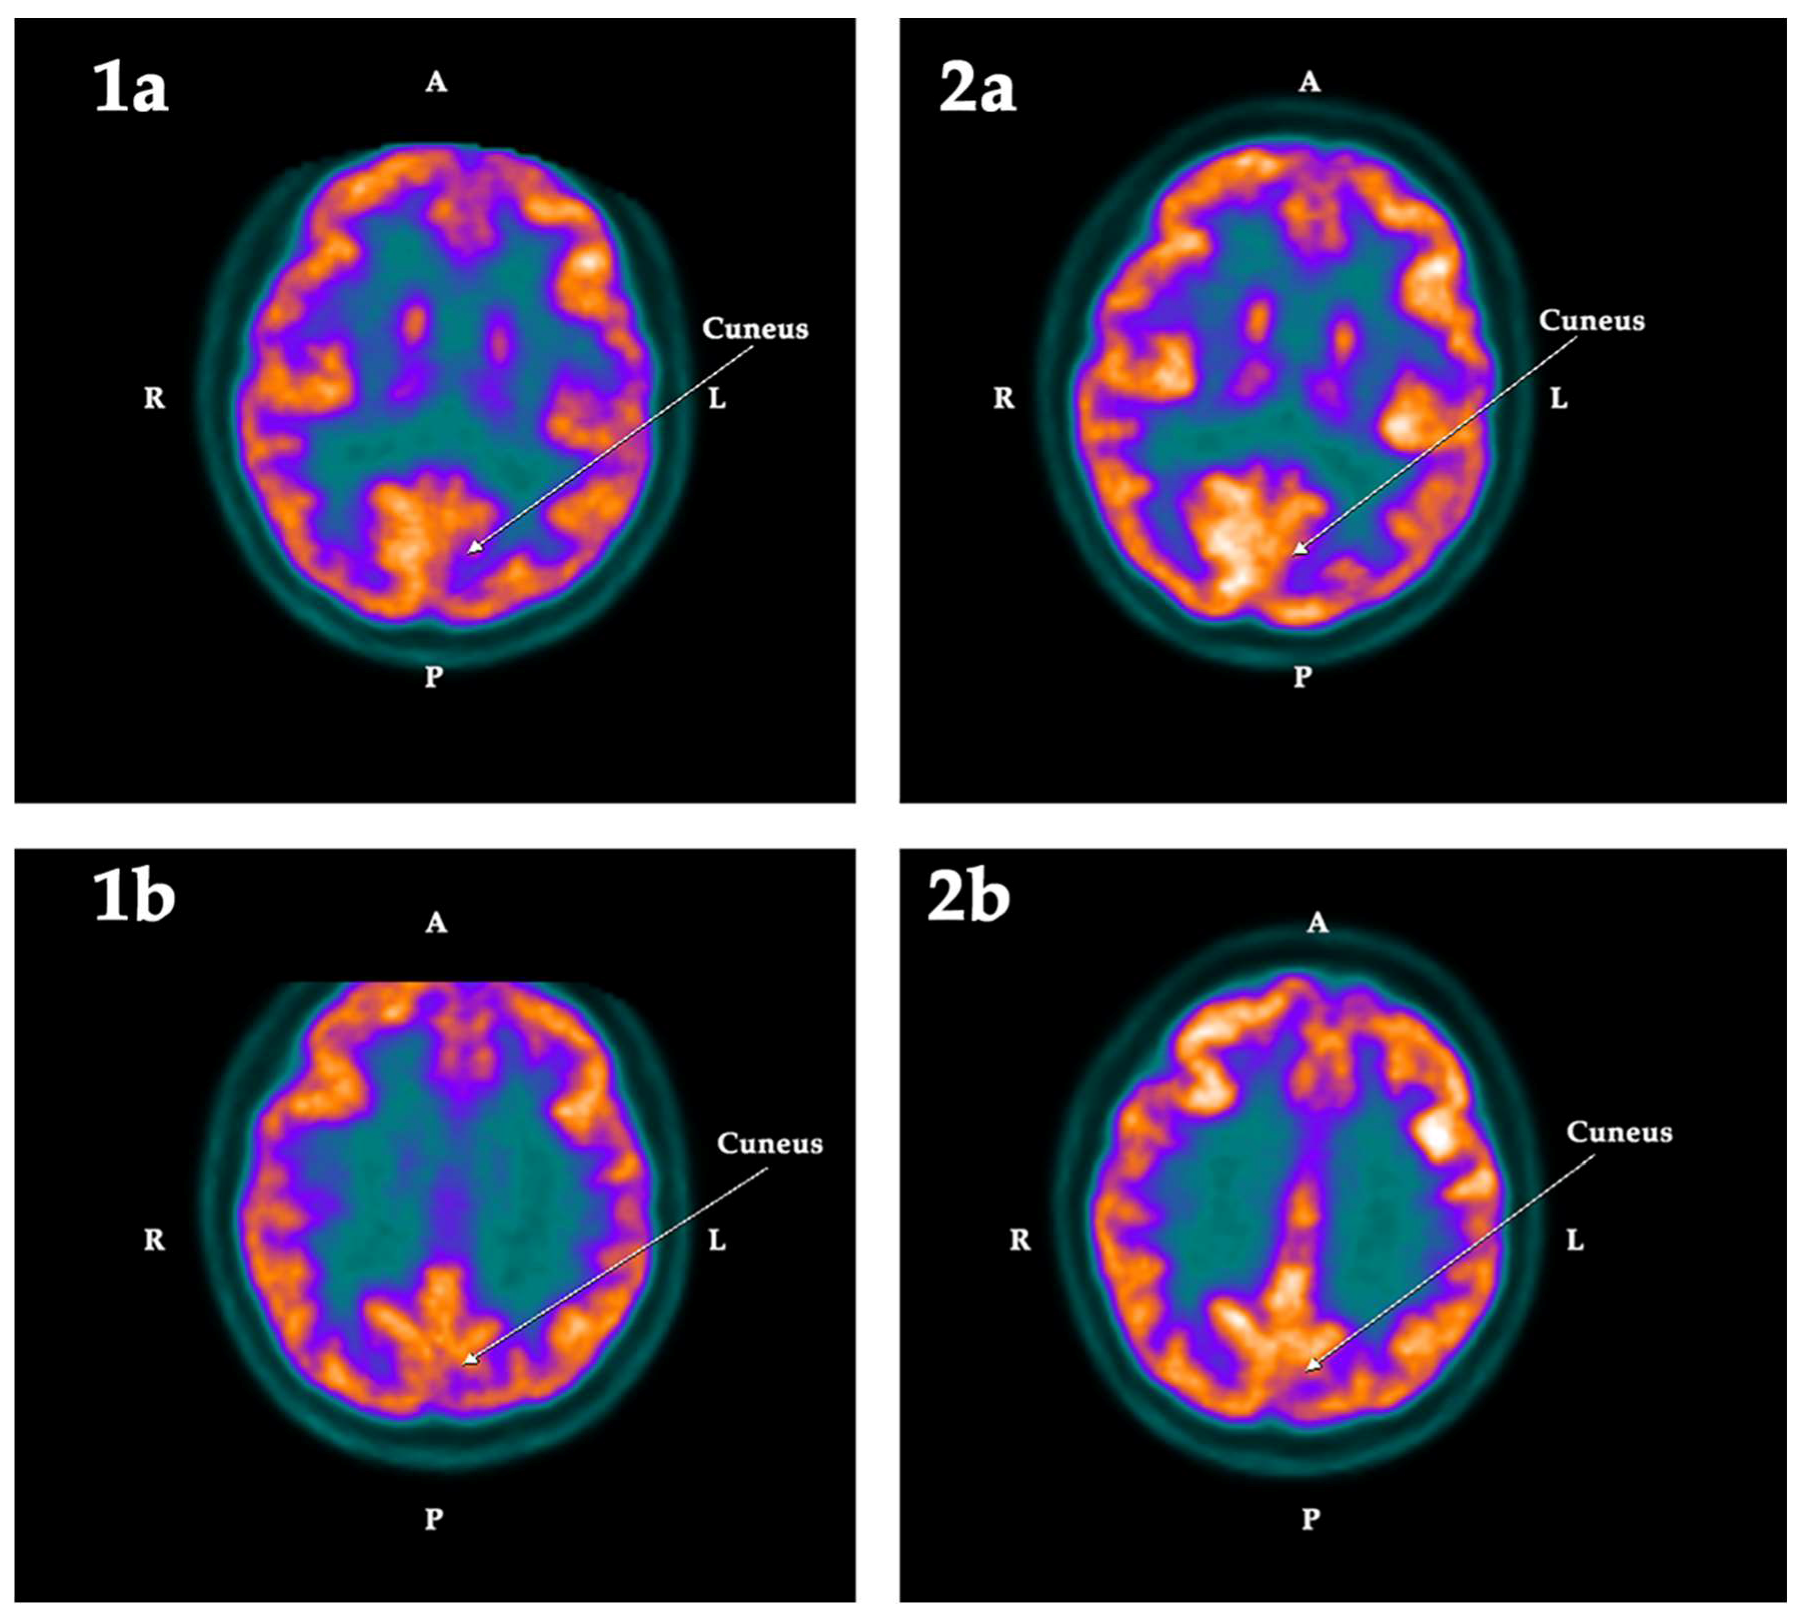

2.2. PET-SCAN Studies

| ROI | First PET-SCAN | p < | Second PET-SCAN | ||||||

|---|---|---|---|---|---|---|---|---|---|

| L | R | Asym | Hypom | L | R | Asym | Hypom | ||

| Cuneus | −5.42 | 4.06 | −9.48 | Left | 0.025 | −0.90 | 6.41 | −7.31 | Left |